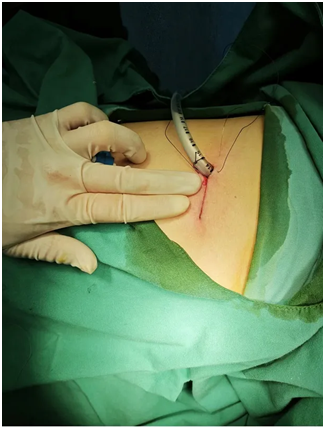

在全面告知病情及后续治疗方案后,小李决定接受单孔胸腔镜手术治疗。手术进行得非常顺利,小李大约一个小时就回到了病房。术后很快拔除了身上引流管,身体恢复得也很好,很快就回归了校园。

4.外科手术治疗(单孔胸腔镜手术)

简单的肺大疱切除手术时间短,大约十几分钟,风险也比较小,患者术后恢复很快,一般3-4天可以出院。